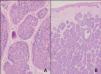

Figura 4. A. Tumor mal delimitado de localización dérmica, constituido por nidos y cordones de células basalioides rodeadas por una banda hialina eosinofílica. (Hematoxilina-eosina, x2.) B. A mayor detalle se observa una doble población: una célula periférica con núcleo hipercromático y tendencia a disponerse en empalizada y otra célula de mayor tamaño con núcleo central vesiculoso. (Hematoxilina-eosina, x20.)